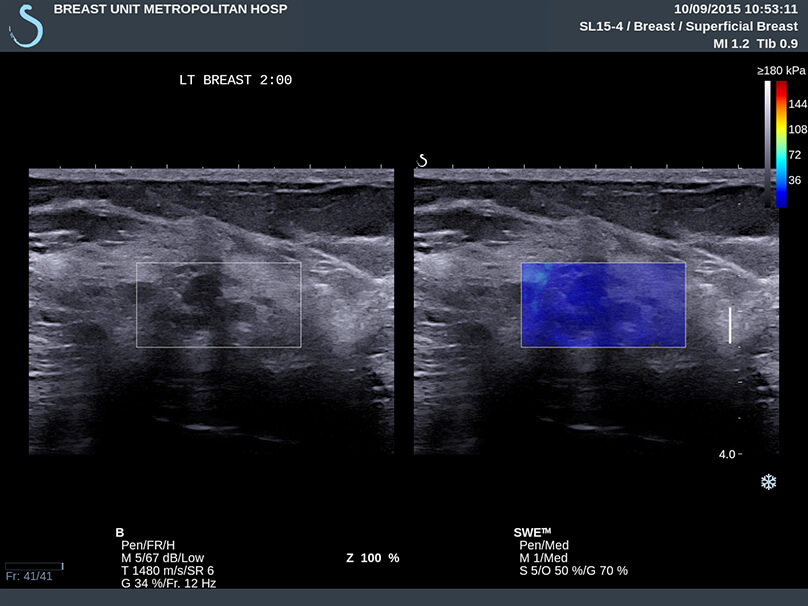

Περιπτώσεις ευρημάτων στο υπερηχογράφημα που μελετήθηκαν περαιτέρω με τεχνική ελαστογραφίας η οποία κατέγραψε μαλακό υπόστρωμα (μπλε χρώμα), που, στις περισσότερες περιπτώσεις, αφορά σε καλοήθεις καταστάσεις του μαστού, απομακρύνοντας ουσιαστικά το ενδεχόμενο της κακοήθειας.